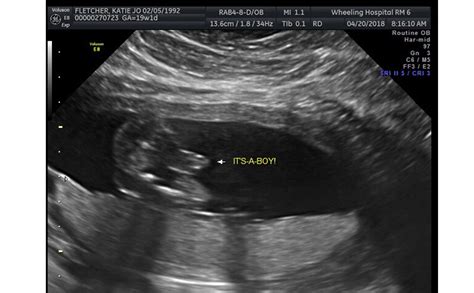

على سبيل المثال، إذا كان الجنين صبيًا، تظهر أعضائه التناسلية بوضوح في الموجات فوق الصوتية، مما يتيح للطبيب التعرف عليها بسهولة.

حيث وجد الطبيب بعد الفحص بالموجات فوق الصوتية أن الجنين فتاة.